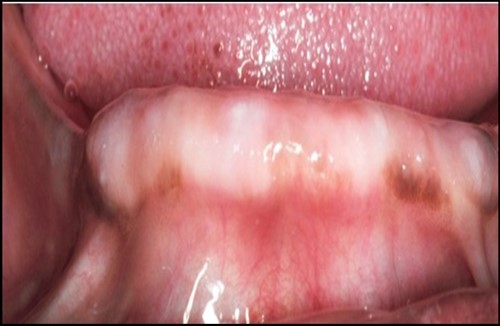

Blood investigations and informed consent was taken after discussing the treatment procedure with the patient and the bystander. Irreversible hydrocolloid impression was made and pre-surgical diagnostic casts were prepared. Inter-occlusal distance was measured in the diagnostic casts. The implant location was marked at B and D positions independent of each other. (Figure 2)

Figure 2.Prpre-operative view of anterior mandibular knife edge ridge.